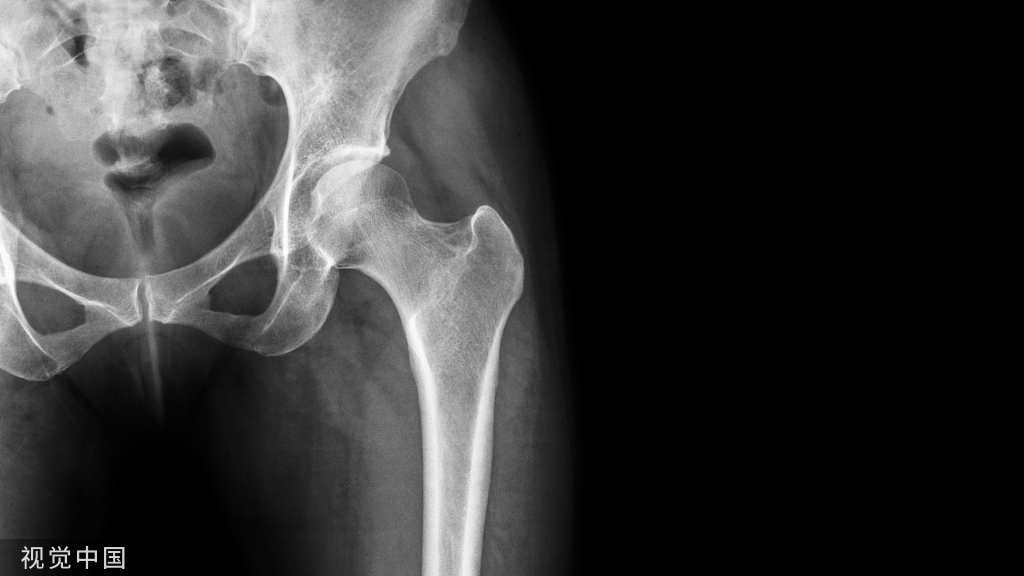

中国下肢骨折术后负重专家共识(2023版)

随着医疗水平的进步及人们对生活水平要求的提高,骨科创伤的治疗不仅需要完成局部组织的修复重建,更需要实现机体的快速康复。针对下肢骨科手术,早期进行合理的负重锻炼是术后管理的重要组成部分。合理负重不仅有助于局部骨质及软组织愈合,还可以促进患者整体机能恢复,提高医疗服务效率。然而,在临床实际操作中,如何让下肢术后患者合理负重一直是困扰医生及患者的难题,业内对于下肢术后负重基本理念及注意要点尚未达成共识。针对此临床问题,由全国创伤骨科专家代表讨论总结了临床中术后负重现有的普遍问题,形成了下肢骨折术后合理负重的基本原则及专家建议,同时列举了针对下肢各部位的负重参考方案,以期指导骨科下肢术后负重临床实践,规范临床研究及相关技术发展,为骨折下肢创伤患者提供更加优质、高效的医疗服务。